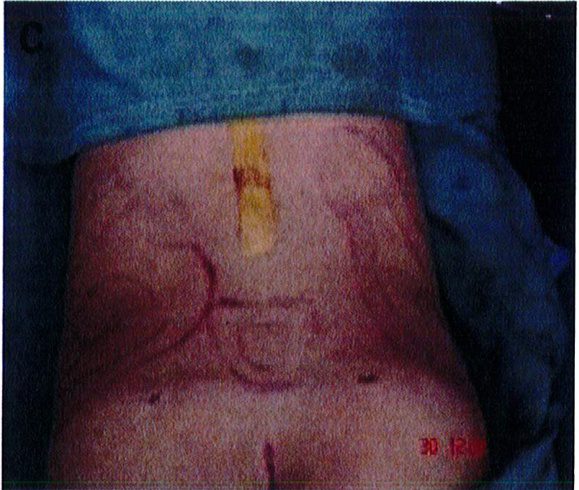

• Để tránh làm đầy phần mông trên quá mức và để xác định mặt phẳng cấy ghép, cần đánh dấu vùng phẫu thuật trước mổ.

Lựa chọn bệnh nhân và đánh dấu vùng phẫu thuật

Tác giả vẫn sử dụng giới hạn dưới của mặt phẳng cắt là 2 đường ngang được vẽ từ đốt xương cụt cuối cùng tới hai mấu chuyển lớn.

Để tránh tình trạng quá ngắn hoặc quá dài của vùng mông (hay còn gọi là mông dài/ngắn) thì tác giả đã kết hợp một phép đo đơn giản trước phẫu thuật, đo khoảng cách từ mào chậu phía sau tới đường ngang đi qua trung điểm nếp liên mông (khoảng cách A) và từ đường ngang đó tới nếp lằn mông (khoảng cách B) (Hình 1) đế tính vị trí chuẩn xác của khối im- plant.

Để tránh tình trạng phần mông trên được nâng lên quá mức, khoảng cách A thông thường phải gấp đôi khoảng B để có thể phù hợp cho nâng mông dưới cơ.

Hình. 1. Đánh giá trước phẫu thuật để lựa chọn bệnh nhân với mặt phẳng im- plant phù hợp.